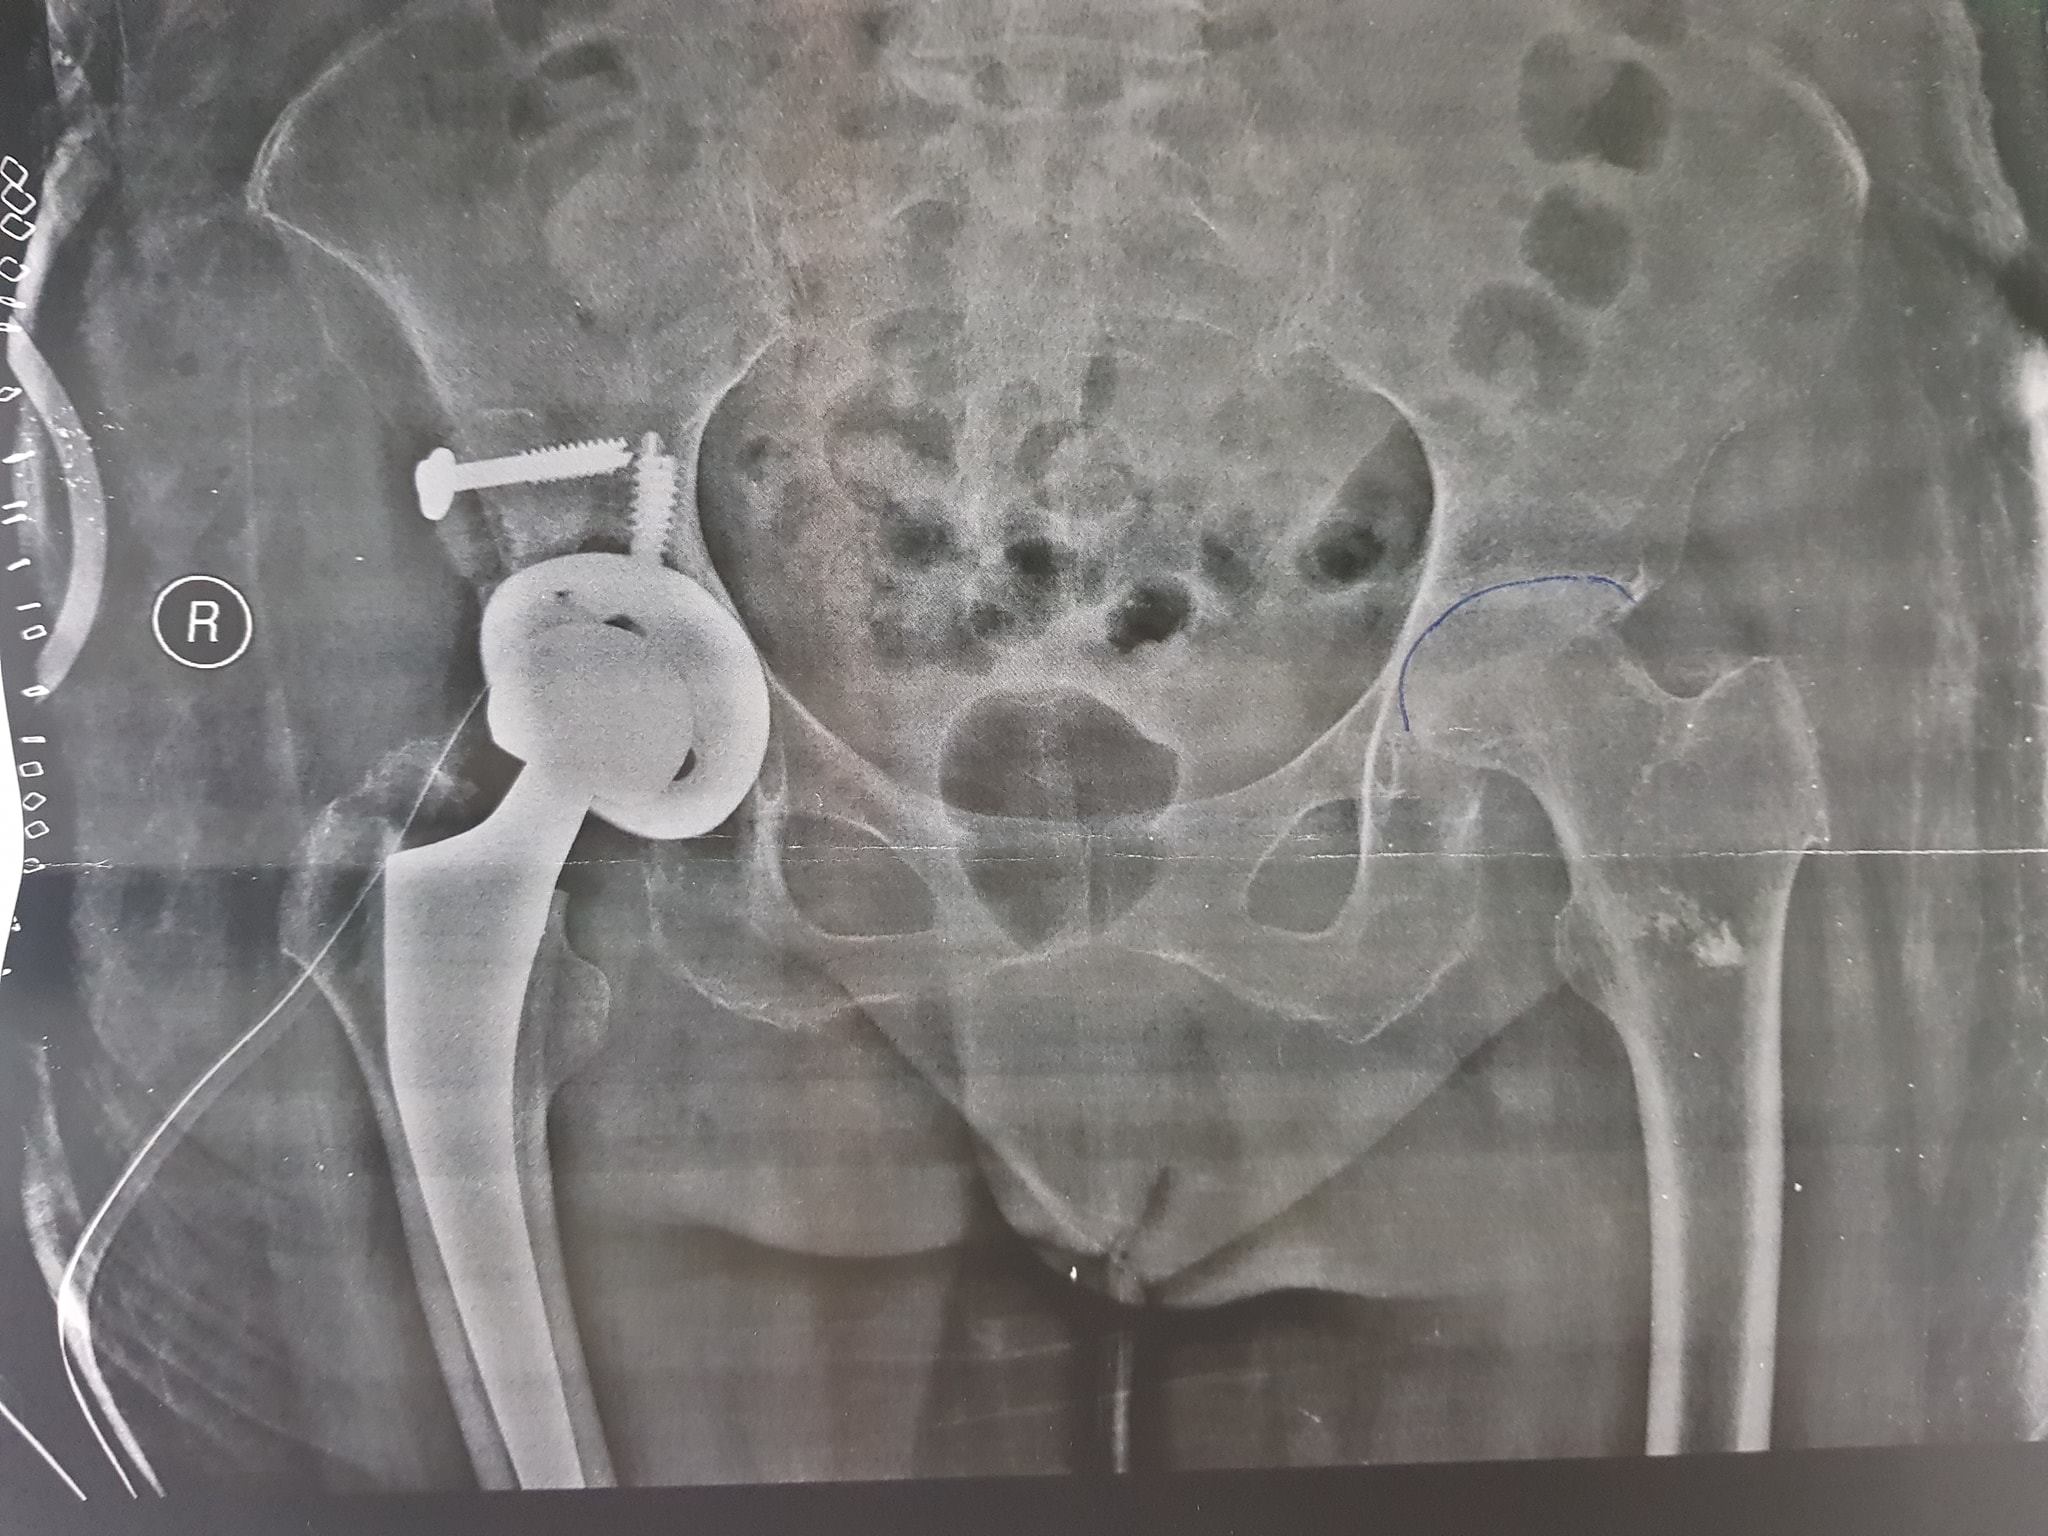

زراعة المفاصل الصناعية ورك و

كافة انواع الكسور وعلاجها

علاج خلع الورك الولادي بكافة ا